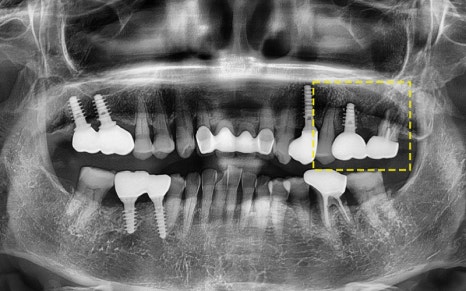

2025.06.18

구강 내 상황을 면밀하게 고려하여

올바른 위치 및 방향대로

임플란트를 잘 식립해주었답니다!

2025.05.31

그래서 저희는 세계에서 가장 오래 쓰이는,

그리고 가장 튼튼하다고 인정받는

스위스 스트라우만 임플란트를 추천드렸고

수술을 진행하였습니다!